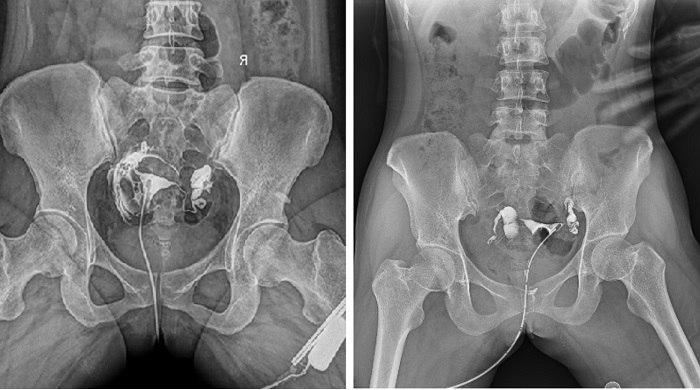

輸卵管造影檢查可根據(jù)造影劑在輸卵管及盆腔內(nèi)的顯影情況了解輸卵管是否通暢、阻塞部位及宮腔形態(tài),是超聲、CT、核磁、宮腔鏡、腹腔鏡、輸卵管鏡等所無法替代的。作為目前普放領(lǐng)域最先進(jìn)的影像設(shè)備,多功能動態(tài)DR進(jìn)行子宮輸卵管造影檢查,大大超越了過去的檢查技術(shù),更加精準(zhǔn)、便捷、高效。

相較于傳統(tǒng)胃腸機(jī),動態(tài)DR矩形采集面積大,一次曝光即可顯示整個盆腔,大幅減少觀察時間,可控的瞬時照射避免受檢者吸收過多的X線,對育齡期女性的檢查尤為重要。毫秒級時間內(nèi)高清點片,可以在造影劑流動的過程中完成拍片,抓拍到關(guān)鍵圖像,更加清楚地了解到管腔的具體通暢情況及堵塞部位,對檢查及診斷有非常重要的價值。

子宮輸卵管造影